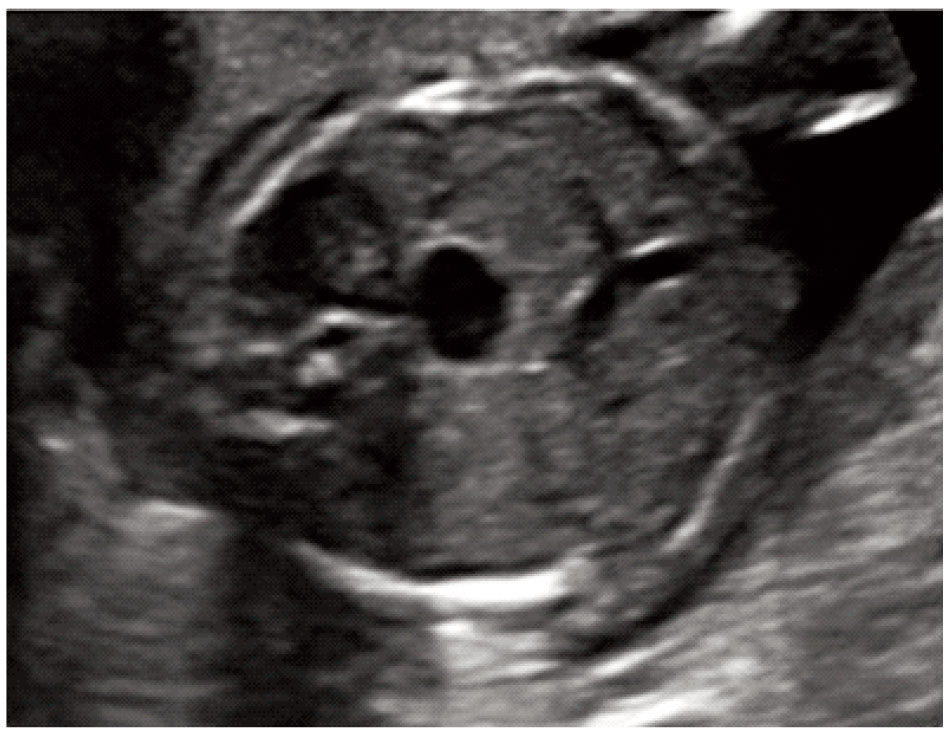

The stomach was present but located centrally rather than on the left side of the abdominal cavity (Figure 1). In addition the cardiac axis deviated to the left. Maternal biochemistry was normal (βhCG: 0.308 MoM, PAPPA: 0.518 MoM) and the risk for the common trisomies was low (1 in 11,941). Repeat ultrasound examination at 17 weeks showed that the stomach remained in central position, there was persistent left superior vena cava and the aorta had obviously smaller diameter than the pulmonary artery (Figures 2, 3). The results were confirmed by fetal echocardiography.Amniocentesis was performed at the request of the parents; the fetal karyotype was normal (46XY) and there were no additional findings from CGH arrays analysis. Fetal MRI at 24 weeks confirmed the central position of the stomach whereas no structural anomaly was detected. Repeat fetal echocardiography at 29 weeks showed normal growth of the aorta and the aortic arch, two morphologically left atria and interrupted inferior vena cava thus establishing the diagnosis of left atrial isomerism. Further investigations by Whole Exome Sequencing detected two missense variants of uncertain significance in the gene PKD1L1. Pathological mutations with heterozygosity in this gene have been associated with autosomal visceral heterotaxy. The parents were counseled by a clinical geneticist on the favorable prognosis in the absence of a heart defect and decided to continue the pregnancy. Repeat MRI scan at 35 weeks identified multiple small spleens and malrotation of the bowel.The infant was born by cesarean section at 38 weeks (birth weight 3,300 gr). The diagnosis was confirmed after birth. He is currently discharged at home and is scheduled for bowel surgery.

Figure 3. Cross‐sectional view of the thorax depicting the three vessel view. Note the smaller diameter of the aorta and the persistent left superior vena carva (white arrow).